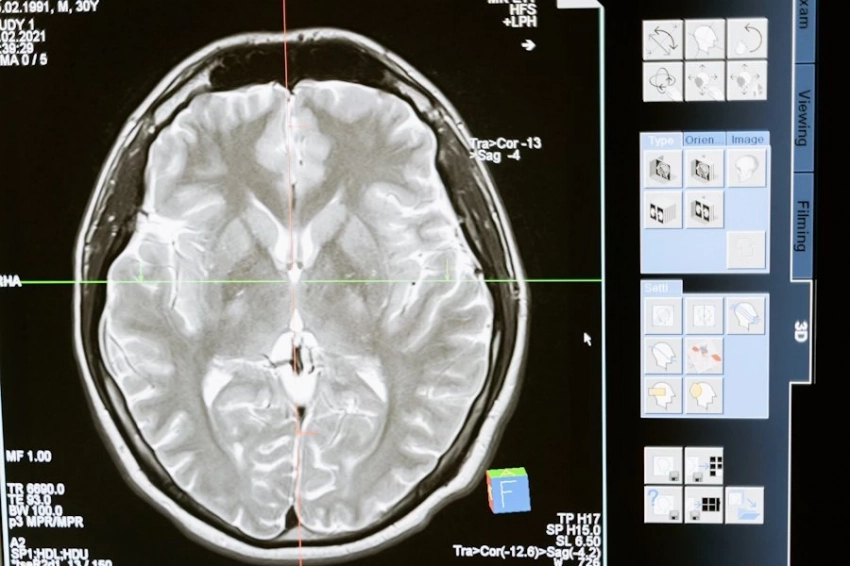

Метод rTMS основан на использовании магнитных импульсов, которые стимулируют определенные участки мозга. Его уже применяют для лечения устойчивой депрессии и изучают как возможное средство против мигреней и табачной зависимости. Хотя механизм действия rTMS до конца не ясен, считается, что он активирует менее активные области мозга, способствуя улучшению когнитивных функций.